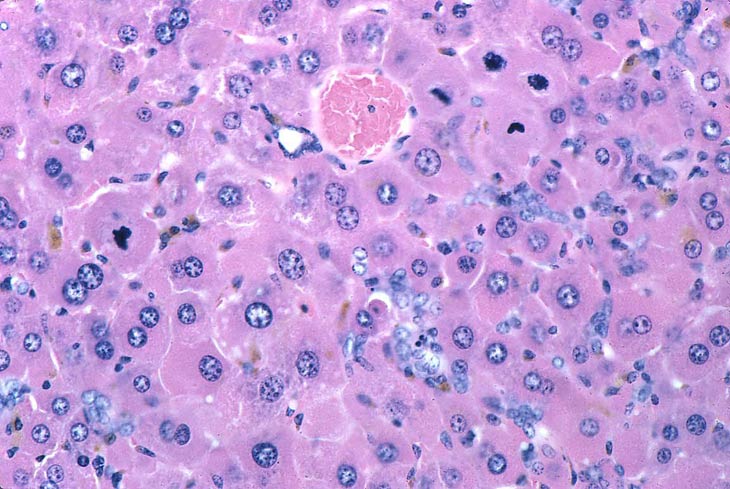

Large eosinophilic hepatocytes (eosinophilic granular cytoplasm represents peroxisome proliferation), biliary hyperplasia (ducts, ductules, oval cells), several mitotic figures, and pigment are present in the liver of this mouse fed a diet containing di-(2-ethylhexyl)-phthalate (DEHP) for 10 months.